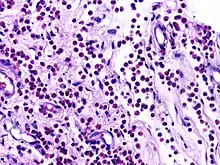

![]() | Eosinophils | Micrograph showing low power view of Eosinophils. | Category: Eosinophils | Eosinophil |